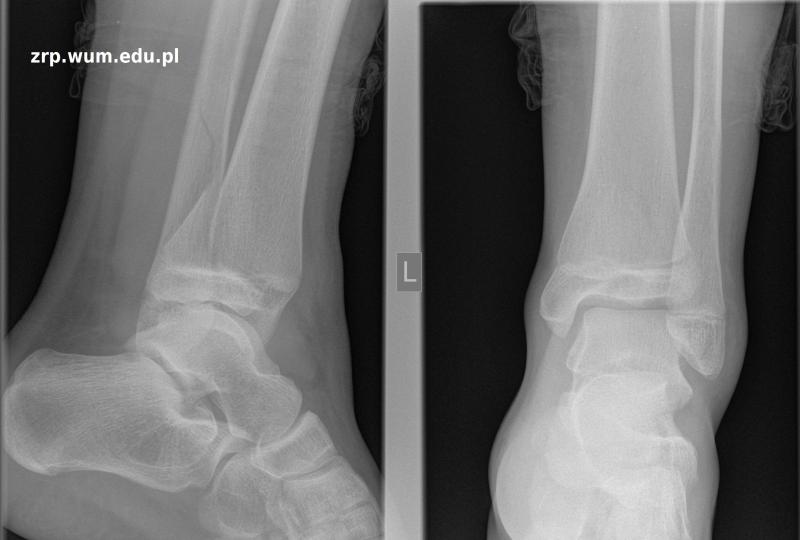

Przypadek 22: 13-letnia dziewczynka spadła z deskorolki. Utrzymuje się duży obrzęk oraz ból lewego stawu skokowego.

Rozpoznanie: W badaniu RTG - złuszczenie nasady dalszej kości piszczelowej lewej (czarne linie), z oderwaniem klinowatego fragmentu kostnego (czerwone linie) od tylnej części przynasady (białe linie). Złamanie kości strzałkowej (żółta strzałka).